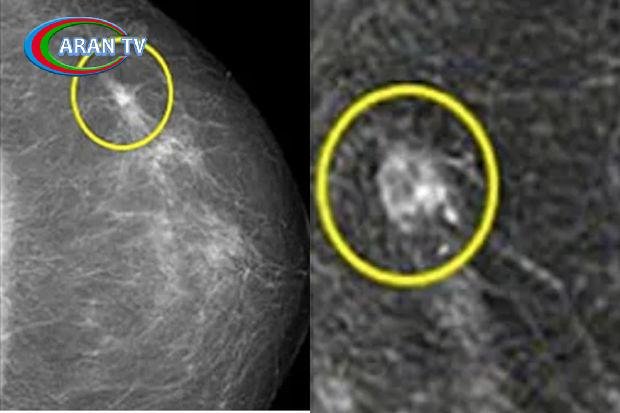

Süd vəzisi xərçəngi qadınlarda ən çox yayılmış xərçəng növlərindən biridir.

Təəssüf ki, xəstəliyin diaqnozu daha çox sonrakı mərhələlərdə aşkarlanır.

Onkoloq bildirib ki, süd vəzisində adətən ağrı və ümumən özünü büruzə verməyən bərkimə varsa, artıq xərçəngdən şübhələnmək olar. Belə olduğu zaman təcili müayinə olunmaq lazımdır.